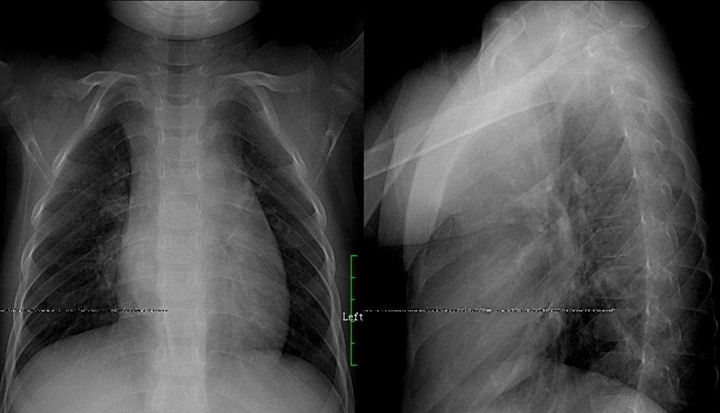

肺結(jié)核:肺結(jié)核分五類型,原發(fā)血播浸結(jié)其,原發(fā)肺內(nèi)淋巴引,血播急粟三均勻,慢播新老病灶模糊,浸潤滲出片絮球,慢纖空洞蜂窩柳,胸膜炎見結(jié)核多,確定三期療效后估,臨床影征痰檢為依據(jù),菌量毒性免疫力,鑒別診斷炎性先,肺癌轉(zhuǎn)移假瘤辨。備注: 蜂窩柳---一形如蜂窩狀肺紋理呈垂柳征。